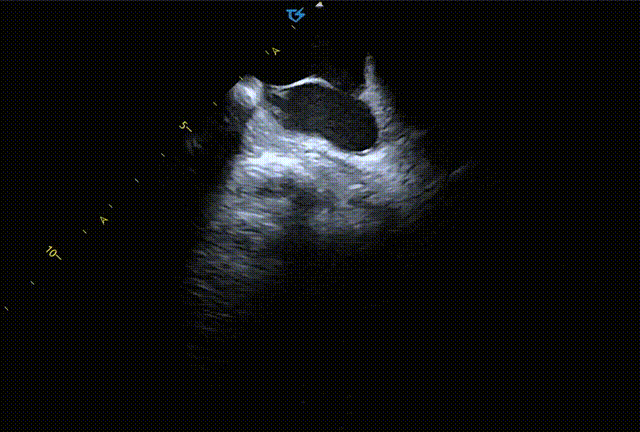

图1 ICE观察室缺形态[1]